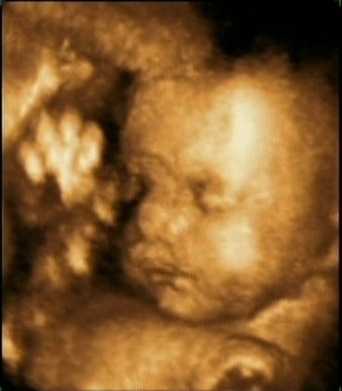

Mi jól vagyunk, a fiam sokszor mocorog, nagyon szeretem érezni! Lányok, mindenkit üdvözlök, akinek nem írtam is persze, igyekszem még a hétvégén benézni!